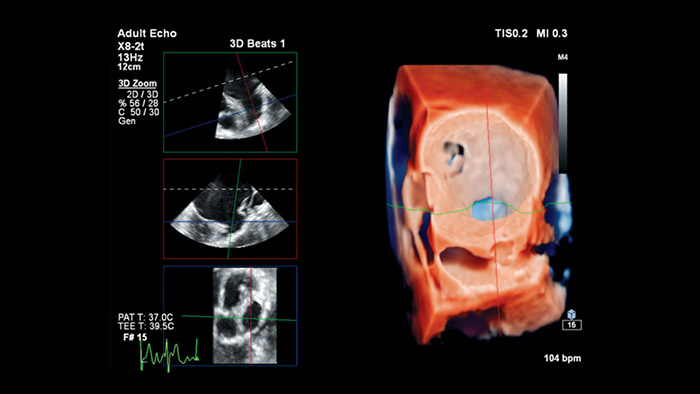

TrueVue

Philips Cardiology TrueVue bevat een virtuele lichtbron waarmee het eenvoudiger wordt om de locatie van defecten te visualiseren en inzicht te krijgen in de diepte van de structuren. Dit leidt tot betere visualisatie van de anatomie tijdens transthoracale en transoesofageale echografie.